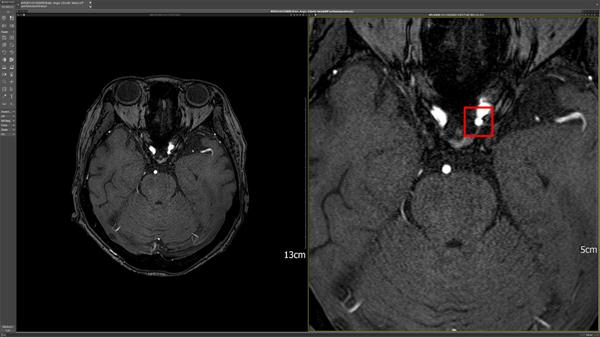

DEEP:NEURO uses AI to help medical professionals diagnose brain aneurysms in brain MRA images. It provides consistent results for the condition, convenience, and accuracy in image reading so that medical professionals can respond and treat cerebrovascular diseases at the right time.